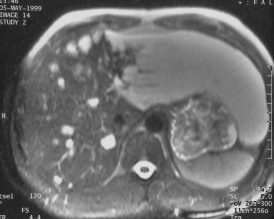

Ce patient est porteur d'angiomes multiples dont un angiome géant du lobe gauche

L'aspect est ici caractéristique, franchement hyper T2 et hypo T1 Prise de contraste en motte très denses. La totalité de l'angiome fini par se remplir sur les coupes très tardives.